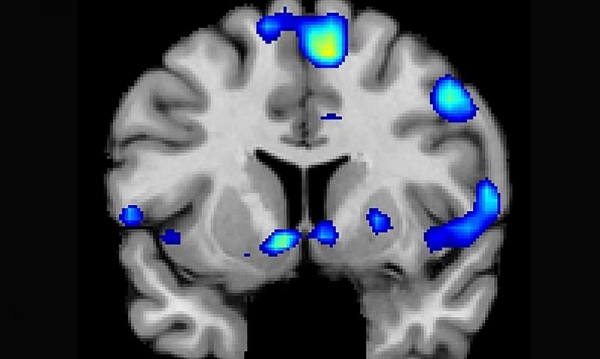

猶他大學研究團隊邀請了 19 名虔誠的摩門教教徒進行實驗,並在過程中利用功能性磁振造影(fMRI)進行腦部活動偵測。實驗中,研究團隊讓他們觀看或聆聽由耶穌基督後期聖徒教會(LDS Church)所推出的經文、圖像或布道影像,藉由此過程讓他們的腦部接收到與宗教有關的訊息。

而在此過程中,研究團隊發現,宗教信仰能夠讓參與者腦部的伏隔核(nucleus accumben)產生可再生的刺激,而其中伏隔核就是能讓人類感受到獎賞、快樂、笑、成癮、侵犯、恐懼以及安慰劑等效果的大腦部位。此外,他們也發現大腦中掌控專心程度、新奇與重要事情理解力的部位也會在此過程中受到刺激。

圖為實驗中受試者的大腦功能性磁振造影圖像,研究人員發現受試者在接觸到宗教信仰時,腦部掌管獎賞和成癮的部位會有反應。